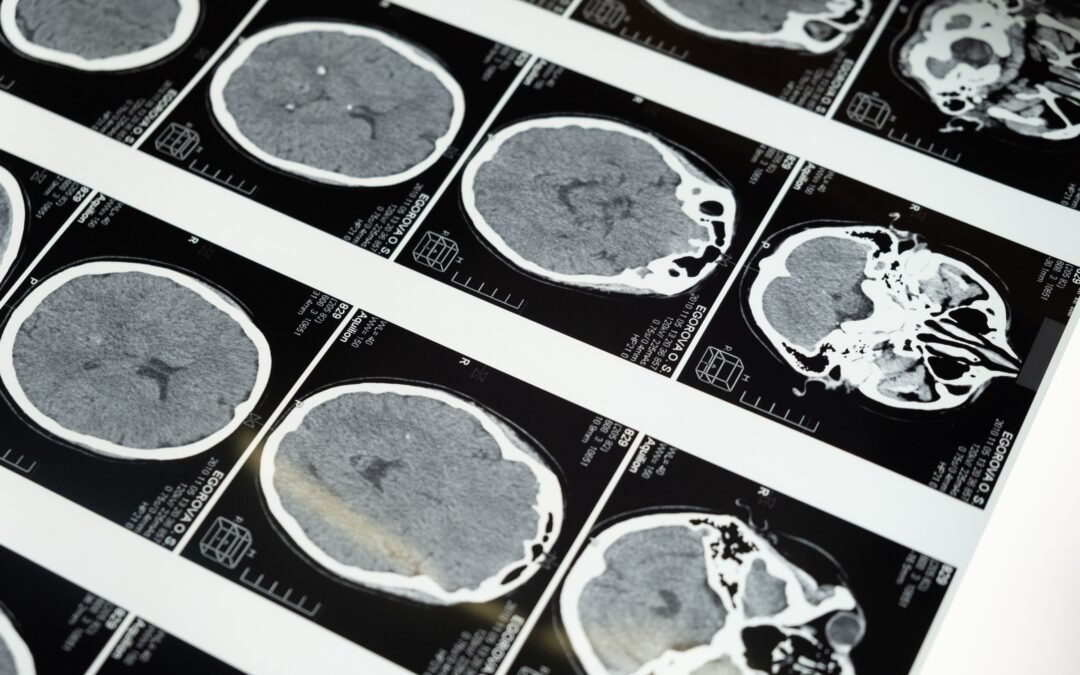

To first understand how the brain works, we have to take a quick look at biology. According to Virtue Baby, a brain works by processing information by forming networks of specialized nerve cells, and these are called neurons. These neurons send messages throughout the entire body and the messages are sent by synapses. There are gaps between the neurons when a baby is born, and the synapses are what get those messages across from neuron to neuron.

When a baby is born, the gap between neurons is very wide, but as they near their first birthday, these gaps fill in making it easier for the brain to send messages.